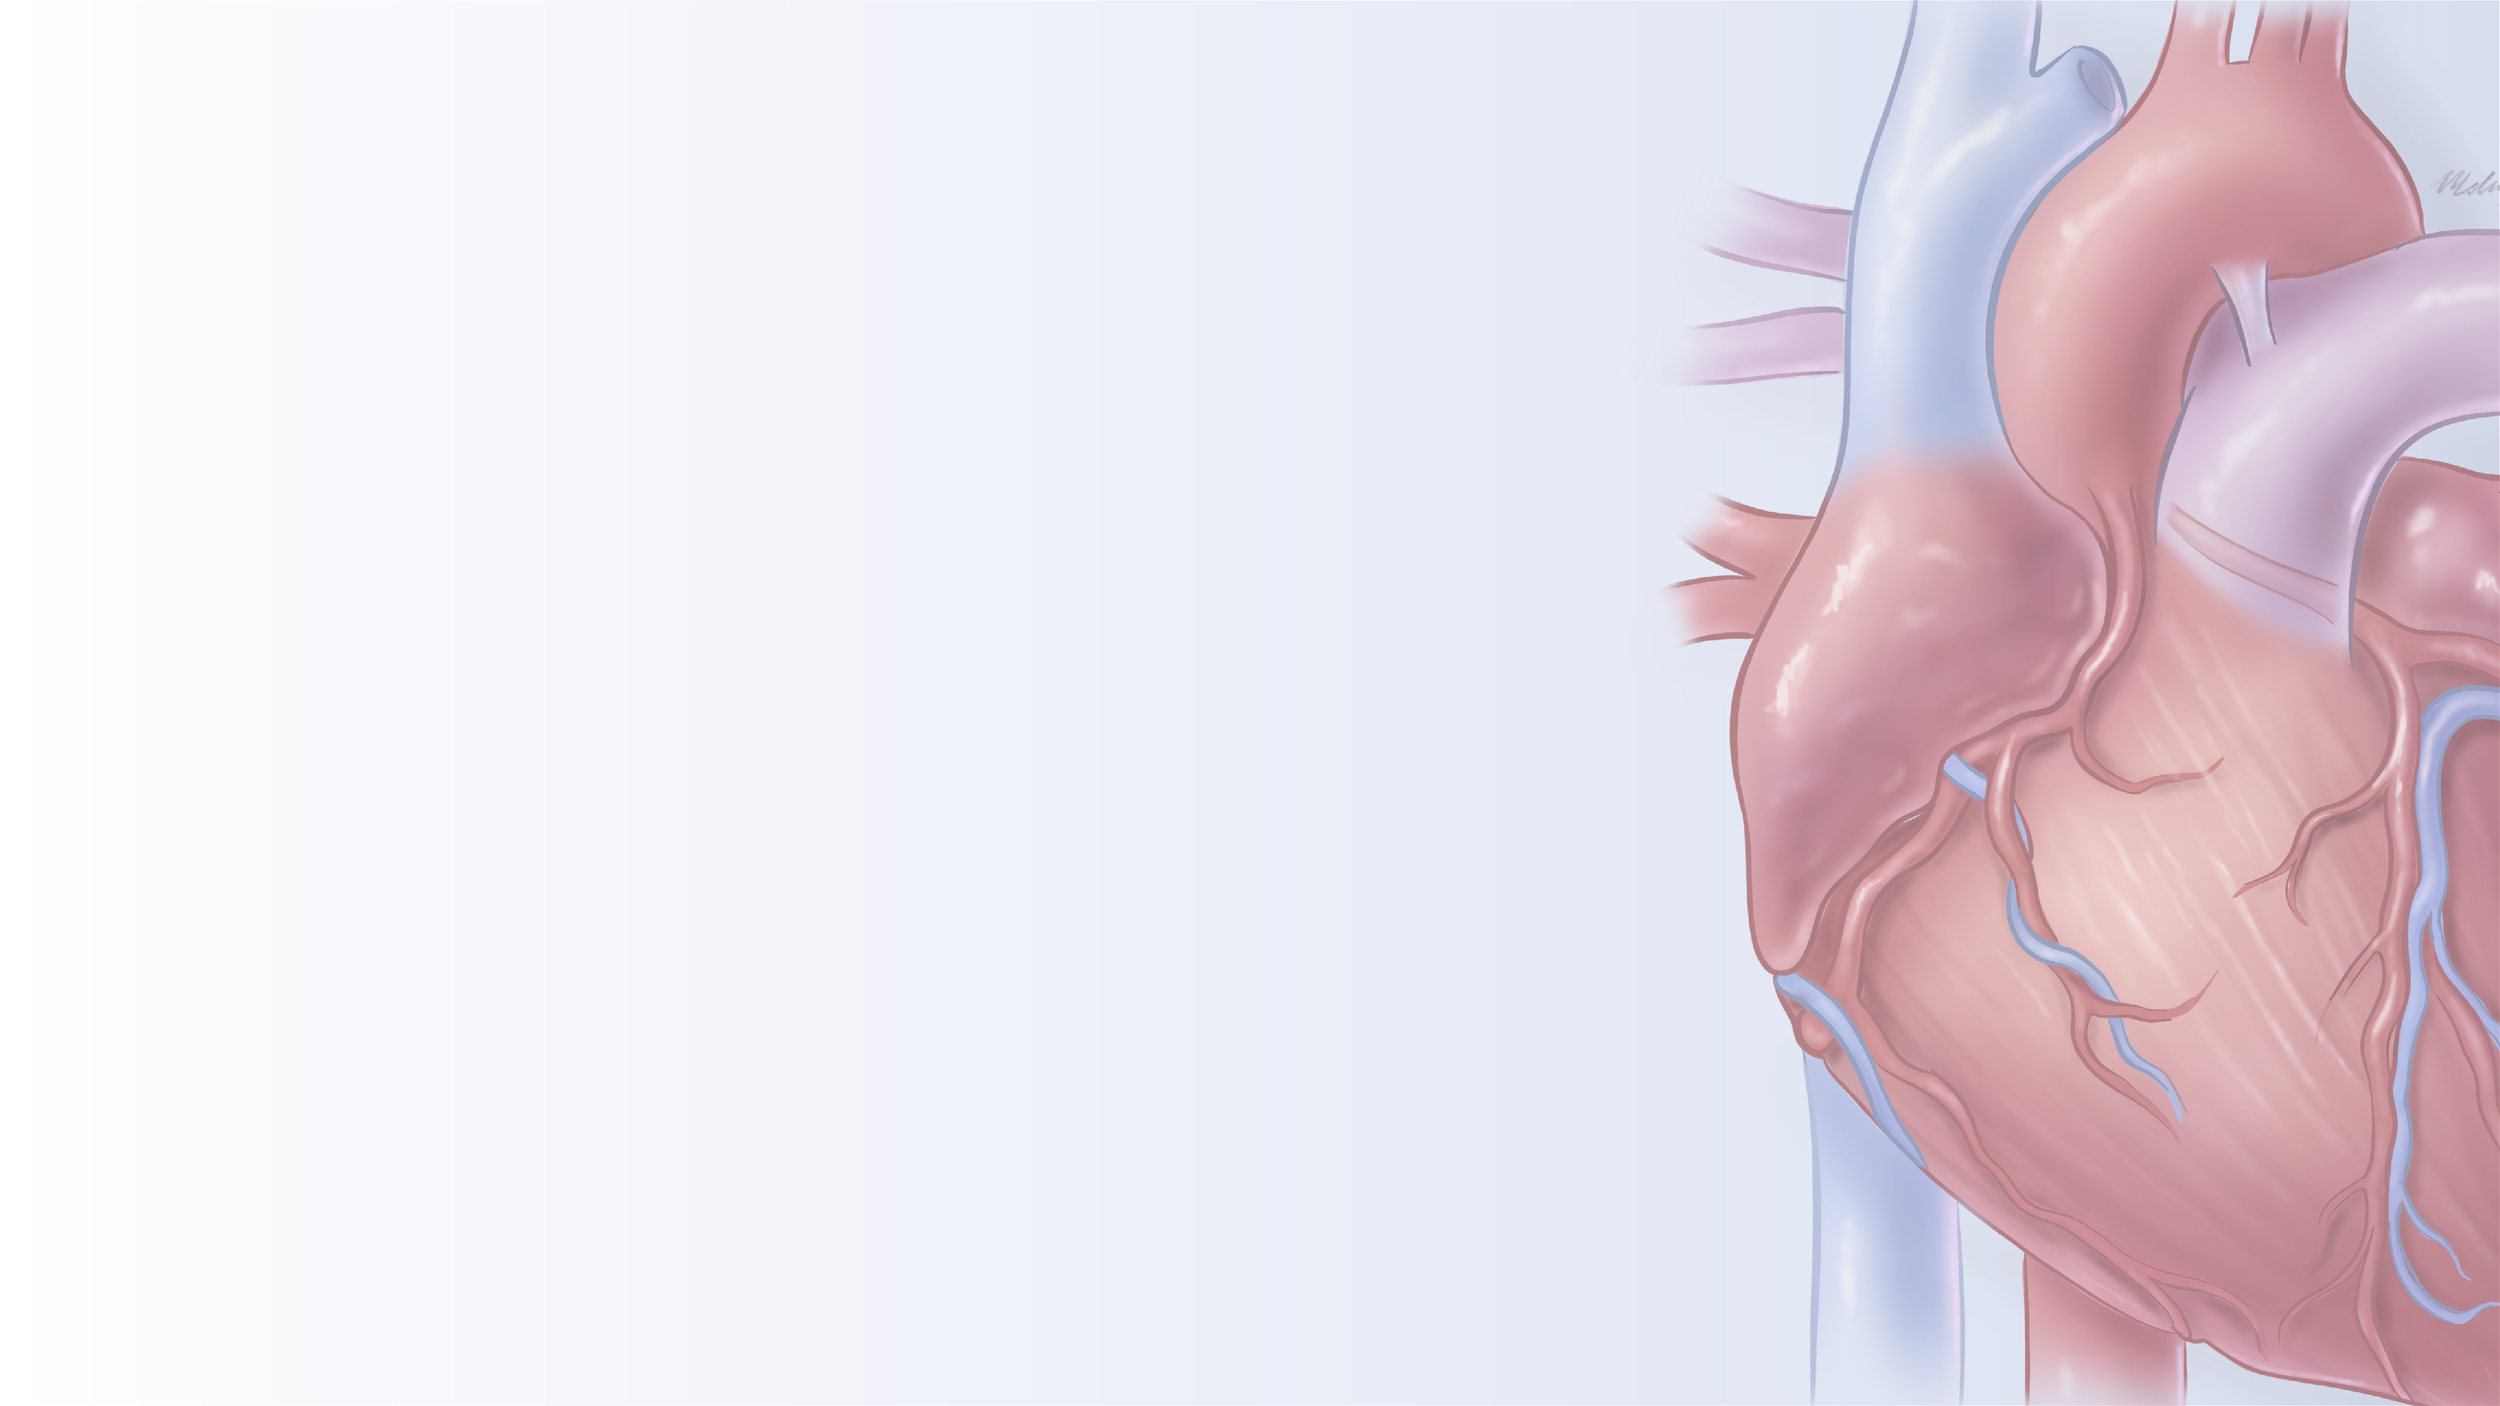

Organ study: The human heart in a painterly style